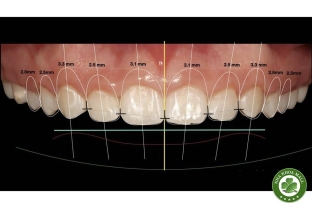

• Chỉnh nha: Niềng răng mắc cài, niềng răng trong suốt, khí cụ chỉnh nha.